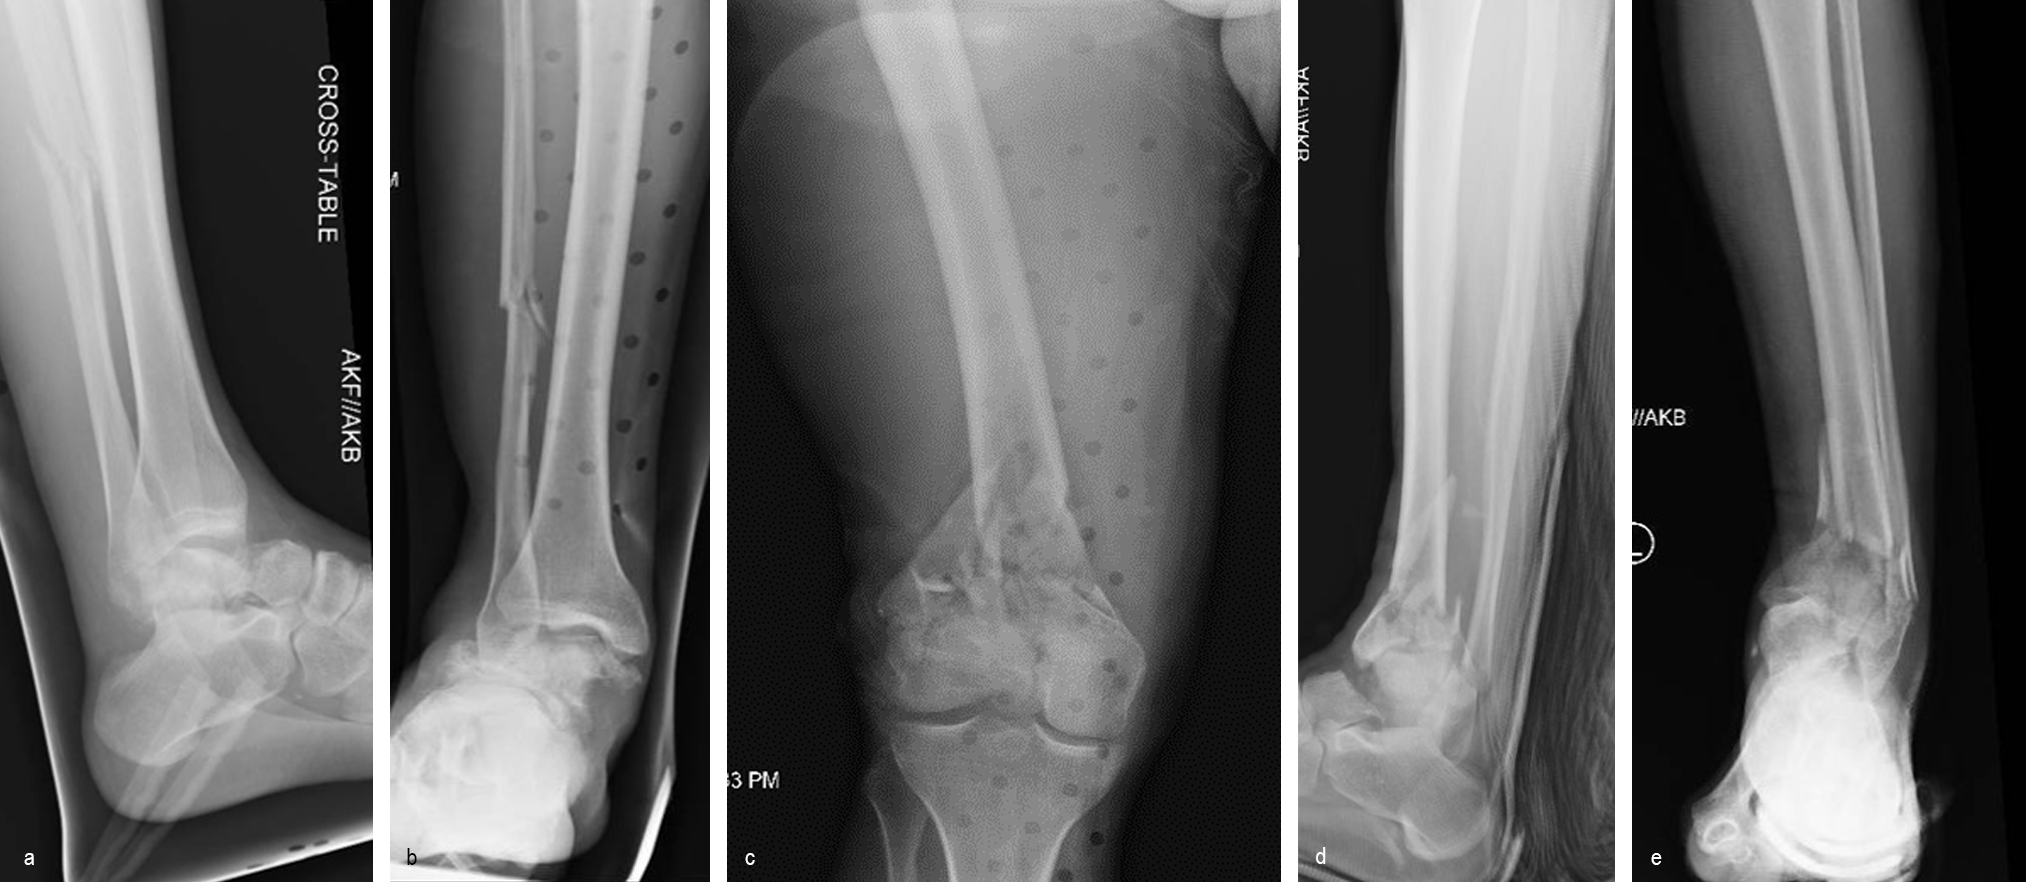

A 34-year-old man was involved in a motor vehicle accident in December 2019 and sustained these injuries (Fig 5):

> Left-sided rib fractures with lung contusion

> Open right supracondylar intracondylar distal femoral fracture with possible vascular injury (limb-threatening injury)

> Closed right bimalleolar ankle fracture

> Closed right talar fracture

> Open left plafond fracture

> Open left talar fracture dislocation

> Open left elbow joint

He had no major previous medical history and worked in the furniture delivery business.

The day following admission, the patient underwent these procedures in the operating room (Fig 6):

> Washout of open injuries right side, including femur and ankle

> Open reduction of the talar injury

> Spanning external fixator of the femur and ankle

> External fixation of the left plafond/talus

At 3 days postoperative, the patient underwent a repeat washout of the right femur and right ankle. The lung injury was still recovering so no definitive fixation was performed at this time.

At 5 days post-initial surgery, the lung injury was improved, so the patient underwent open reduction and internal fixation (ORIF) of the right distal femur with resection of devitalized bone and cement spacer placement (Fig 7). Definitive fixation of the other fractures (ankle and ribs) was undertaken over time.